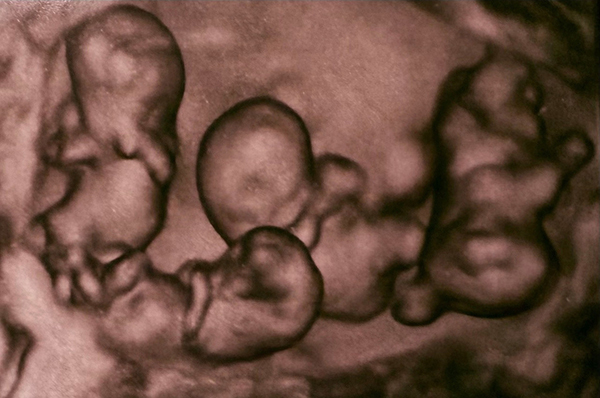

Moscú.- El 2 de abril nacieron en San Petersburgo unas cuatrillizas monocigóticas, es decir, cuatro bebés idénticas provenientes de un solo óvulo fecundado, un hecho sin precedentes en la historia de la medicina de Rusia, recogen este domingo medios locales.

El acontecimiento tuvo lugar en el hospital de maternidad Nº.17, de la ciudad rusa. Las cuatro bebés nacieron a las 32 semanas de gestación. De acuerdo con especialistas, este tipo de embarazo es extremadamente raro, ya que se estima que ocurre una vez cada 15,5 millones de partos.

Un equipo de obstetras, anestesiólogos y neonatólogos encabezados por el director del hospital realizó la compleja intervención, garantizando la seguridad de la madre y las recién nacidas. De acuerdo con la institución médica, las niñas presentaron condiciones de salud acordes a su edad gestacional, con pesos que oscilaron entre 1,36 y 1,64 kilogramos.